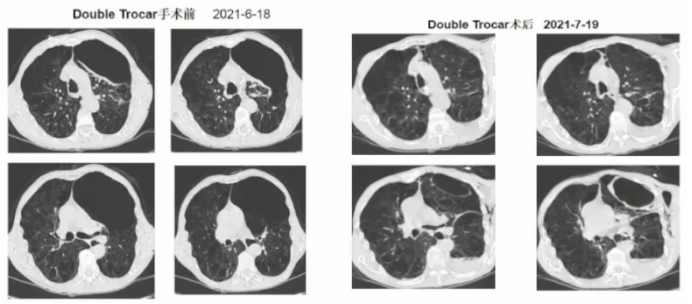

笔者团队最初设计“Double-Trocar”内科胸腔镜下肺大疱减容术时是通过CT明确肺大疱位置,然后进行局部穿刺(定位),随后立即去内镜室进行减容。随着技术的成熟,目前的方法经过改良,已经不需要通过CT进行穿刺。图1所示为2021年笔者团队第一例接受“Double-Trocar”内科胸腔镜下肺大疱减容术的患者影像学变化。术前可见患者左肺上叶巨大的肺大疱,减容术后1个月复查胸部CT可见肺大疱较前明显缩小,局部形成炎症瘢痕。随着时间进展,这种炎症瘢痕还会进一步缩小。术后3年随访,患者状态仍然比较理想。

1  “Double-Trocar”手术前后患者影像学变化